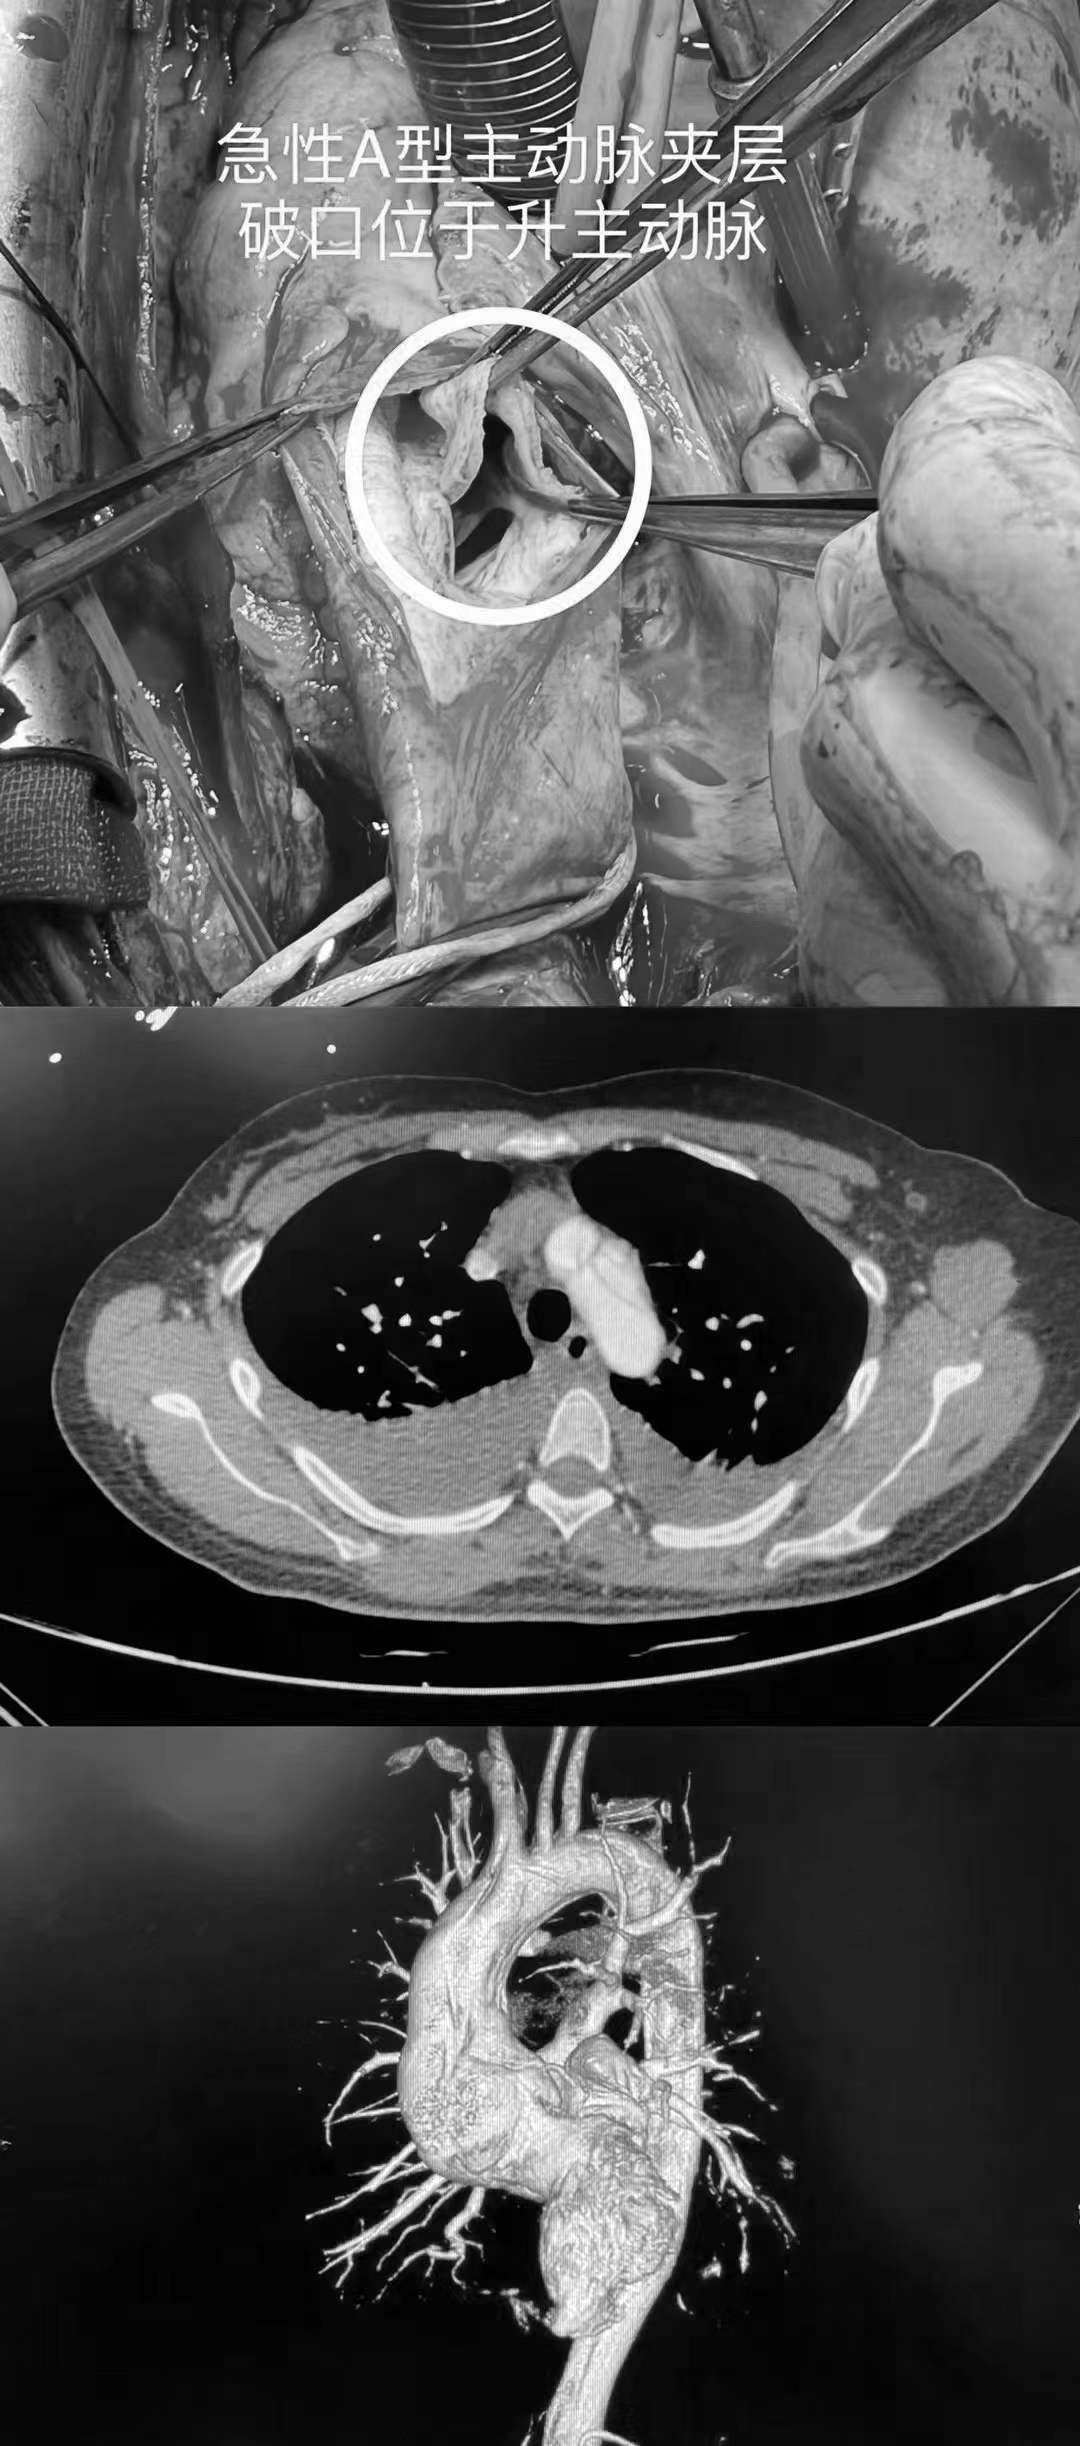

马不停蹄地为刘女士实施了急诊右冠主干冠脉搭桥术 bentall手术 孙氏

图片尺寸1080x2446

隔膜型主动脉瓣下狭窄切除术

a:白塞氏病患者内衬固定环加固的bentall手术 la:左心房,mv为二尖瓣